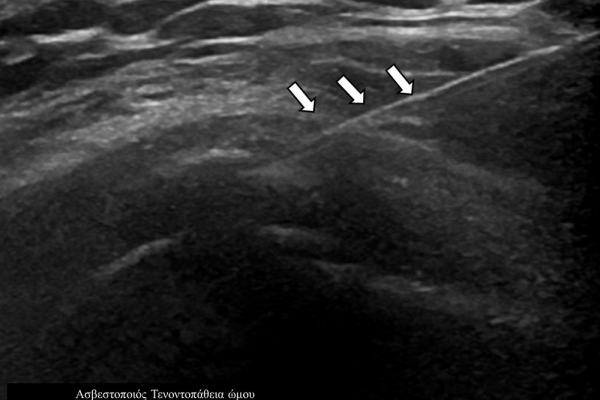

Η ασβεστοποιός τενοντοπάθεια-τενοντίτιδα είναι η εναπόθεση αλάτων ασβεστίου μέσα στους τένοντες,πιο συχνά του στροφικού πετάλου του ώμου, με αποτέλεσμα την τοπική φλεγμονή και πιθανή ρήξη του τένοντα.

Η υπερηχογραφικά καθοδηγούμενη αφαίρεση των επασβεστώσεων (barbotage) είναι μια ελάχιστα παρεμβατική (minimally invasive) τεχνική θεραπείας για την ασβεστοποιό τενοντοπάθεια. Με τους υπερήχους είναι δυνατός ο εντοπισμός των ασβεστώσεων και η διαδερμική τοποθέτηση μιας βελόνας στο κέντρο της συμπτωματικής ασβέστωσης. Στη συνέχεια γίνεται διαδερμικός τρυπανισμός και επαναλαμβανόμενες πλύσεις του ασβεστίου, με αποτέλεσμα τόσο την αφαίρεση της παθολογικής επασβέστωσης όσο και την αυξηση τοπικά της αιμάτωσης με αποτελεσμα την σταδιακή απομάκρυνση των παραγόντων φλεγμονής-ερεθισμού.